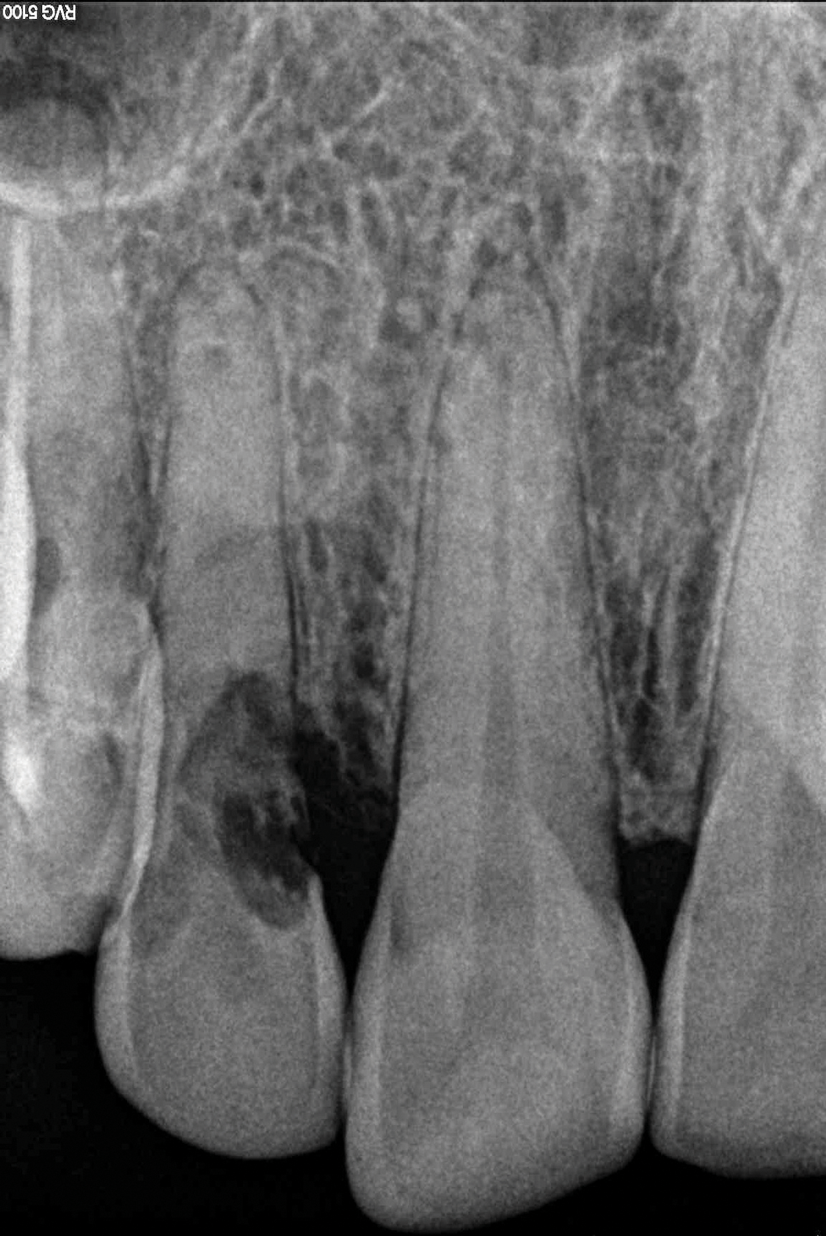

Depending on whether patients present with an existing edentulous space or a non-restorable tooth requiring extraction, as well as other factors, their long-term treatment goals may vary. Nonetheless, each case should be evaluated to identify patients' needs regarding immediate restoration. In the example case presented here, a radiographic examination of a discolored canine lead to the discovery of a lateral incisor (tooth No. 7) with internal resorption that required extraction (Figure 1). The tooth was extracted, and an implant was subsequently placed (Figure 2); however, the patient would be unable to complete the treatment for an extended period of time, so a fiber-reinforced composite bridge was chosen to serve as an ideal long-term provisional replacement option.

(1.) Pretreatment radiograph of tooth No. 7 showing an internal resorption lesion.

Figure 1